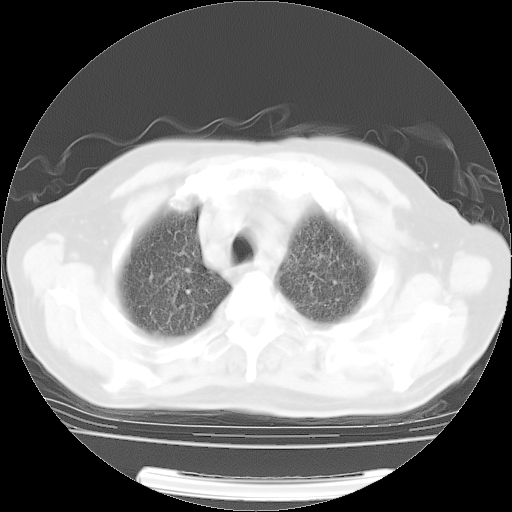

4月14日肺部CT